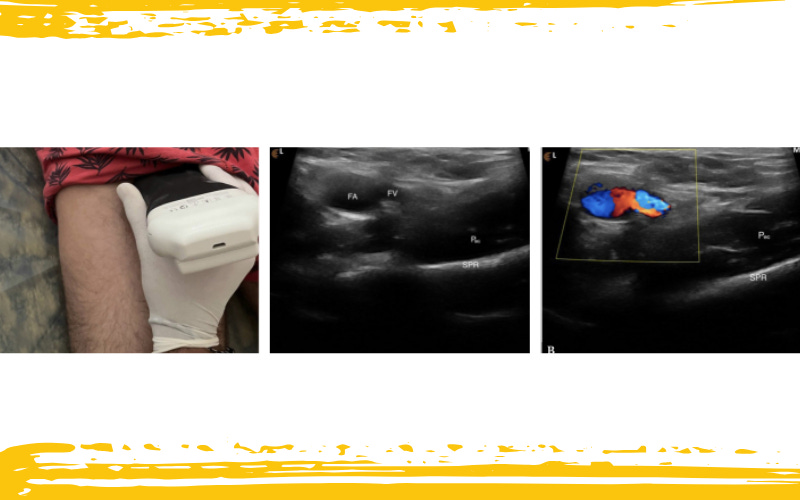

Desde ahí, se rota la sonda al plano longitudinal y se inclina hasta delinear completamente los bordes y cuerpo del músculo. Este paso es crucial, porque sólo con una visualización clara podemos avanzar al siguiente nivel.

Infografía 2. Visualización del ramo púbico superior y del músculo pectíneo medial a la vena femoral en el plano transversal.

M – medial; L – lateral; P – proximal; D – distal; AL – músculo aductor largo;

Ipt – tendón del iliopsoas; FA – arteria femoral; FV – vena femoral;

FN – nervio femoral; OE – músculo obturador externo; Pec – músculo pectíneo;

SPR – ramo púbico superior.